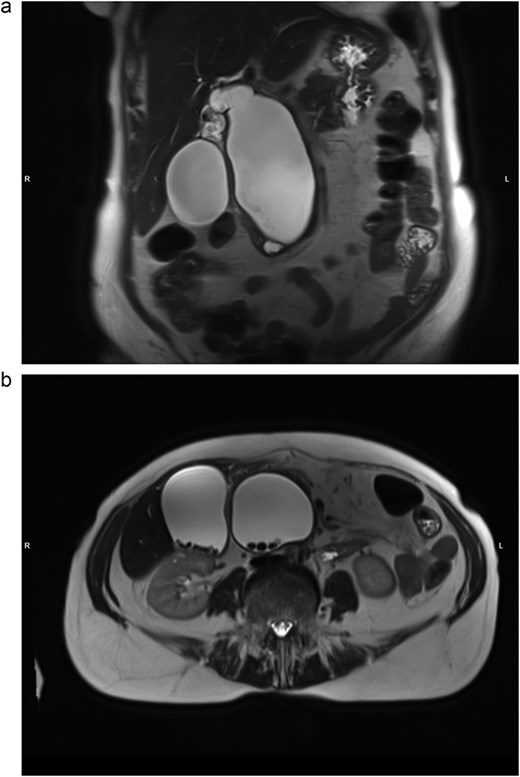

At the time of admission, laboratory findings included alkaline phosphatase of 181 U/L (normal: 40–150 U/L), GGT of 240 U/L (normal: ≤36 U/L), lipase of 318 U/L (normal: 8–78 U/L). MRI of the abdomen showed cystic dilation of the common bile duct (CBD) reaching 13 × 6 × 5 cm with infiltration of pancreatic head and multiple intraluminal fine stones (Fig. 1). Intrahepatic bile ducts, the common hepatic duct (CHD), the cystic duct and the gallbladder were also dilated, the latter contained numerous gallstones. Pancreatic head was pressed and slightly dislocated forward and downward. The bile duct cyst was subsequently classified as Todani type IA choledochal cyst.

MRI, T2-weighted scan. Todani type IA biliary cyst. (a) Coronal slice: cystic dilation of CBD, diffusely dilated biliary tree; (b) axial slice: multiple CBD and gallbladder stones.